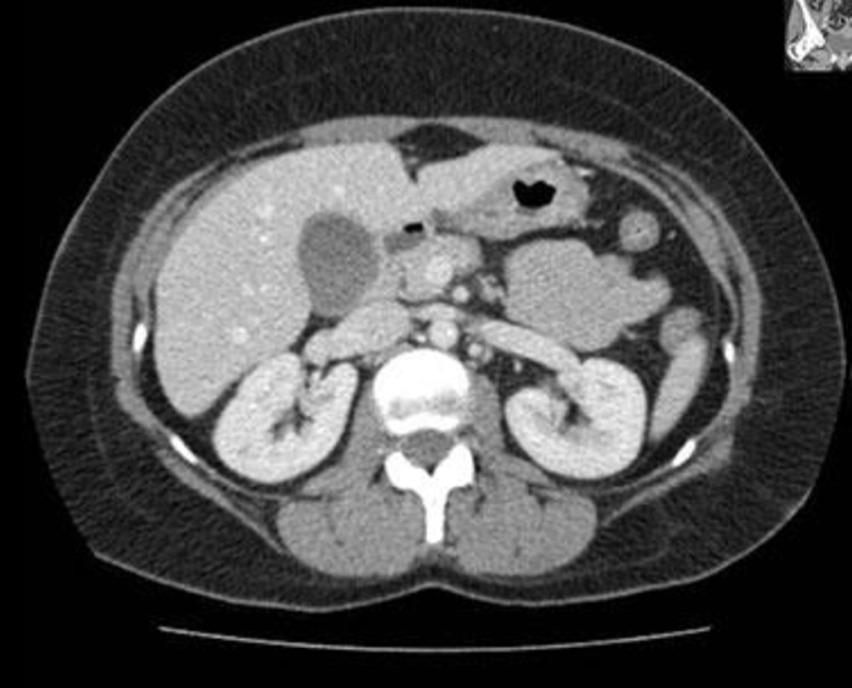

19

Miltraume:

20

Q

Diagnose?